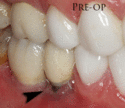

Additionally, for an implant to look esthetic, a band of full, plump gingiva is needed to fill in the space on either side of implant. The most common soft tissue complication is called a black-triangle, where the papilla (the small triangular piece of tissue between two teeth) shrinks back and leaves a triangular void between the implant and the adjacent teeth. Dentists can only expect 2–4 mm of papilla height over the underlying bone. A black triangle can be expected if the distance between where the teeth touch and bone is any greater.[18](pp81–84)